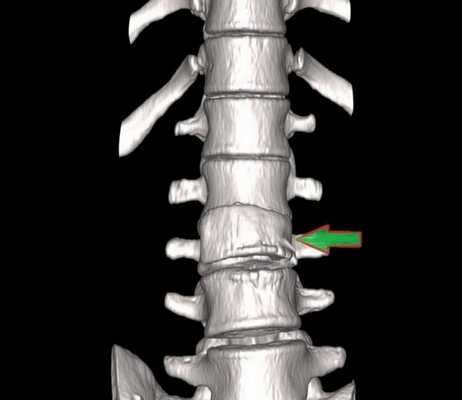

Перелом грудного отдела (трехмерная и сагиттальная проекции)

В результате компьютерной томографии получают серию послойных изображений рассматриваемой зоны. Монохромные фотографии обладают высоким разрешением. В отличие от рентгенографии на снимках отсутствуют дефекты и тени от расположенных рядом структур. Изменение плоскости при реконструкции изображений позволяет тщательно изучить анатомические образования. Преимуществом КТ является возможность создания 3D-модели позвоночника.

Компрессионный перелом (показан стрелкой) поясничного отдела позвоночника

Компьютерная томография позвоночника показывает малейшие нарушения строения и функциональности суставных элементов. Трехмерное изображение при подготовке к хирургическому вмешательству позволяет локализовать патологический процесс, уточнить объем предстоящей операции.

Трехмерная реконструкция при КТ